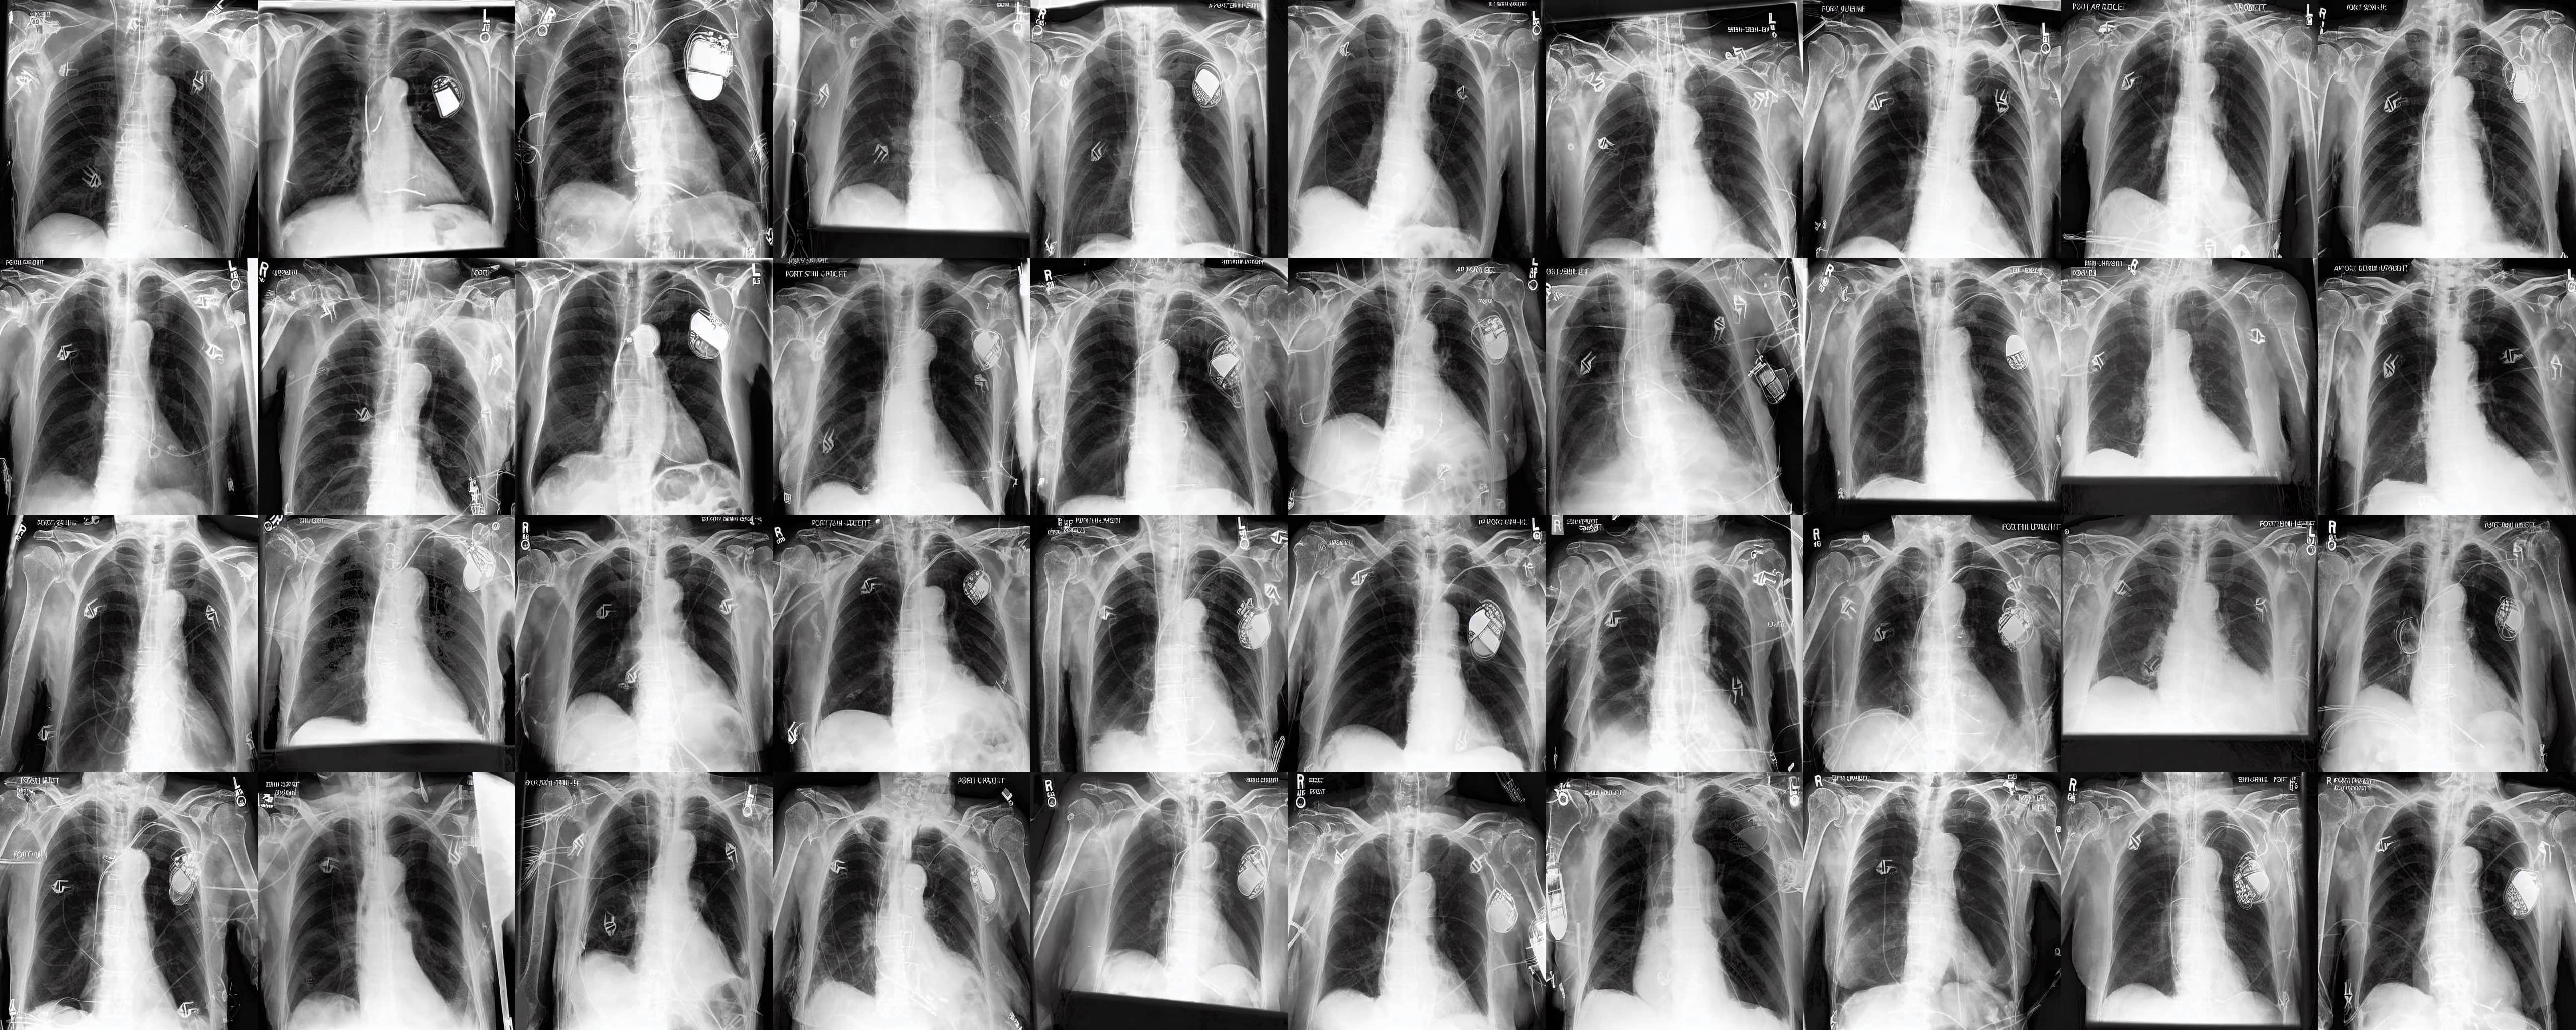

Chest X-rays We use the CheXpert dataset 10.1609/aaai.v33i01.3301590 , which contains 170k training images. This dataset contains diversity in medical devices (such as chest tubes and wires), diseases (such as pneumonia and pleural-effusion) and anatomical details. We implement Rainbow on top of frozen parameters of a finetuned Stable Diffusion v1.5 (SD1.5) by previous work kumar2025prism for chest X-ray data. We generate 2D chest X-ray images based on text prompt conditions, e.g., "Chest X-ray showing Support Devices". In addition to the finetuned SD1.5, we include RadEdit perez2024radedit , a model trained from scratch on multiple chest radiology data such as CheXpert irvin2019chexpert , MIMIC-CXR johnson2019mimic , and NIH-CXR wang2017chestxray data for image editing tasks (more details at Appendix D.3), in the result comparison. Rainbow’s graph generator module includes , , and .

Chest X-rays Figure 4b quantifies generations by Rainbow and baselines using FID and VS. Rainbow achieves a higher VS, indicating greater diversity than the finetuned SD model, while also improving image quality with a lower FID score. Both Rainbow and SD outperform the RadEdit. Figure 6 provides a qualitative comparison, images are generated using the prompt "Chest X-ray showing support devices", where Rainbow generates a more diverse set of medical devices, such as pacemakers, in all generations, while baselines do not show any devices in some images. All models achieve similar CLIP scores of . Additional results including generations, Figure 22 and numeric results, Table 4, are outlined in Appendix E.